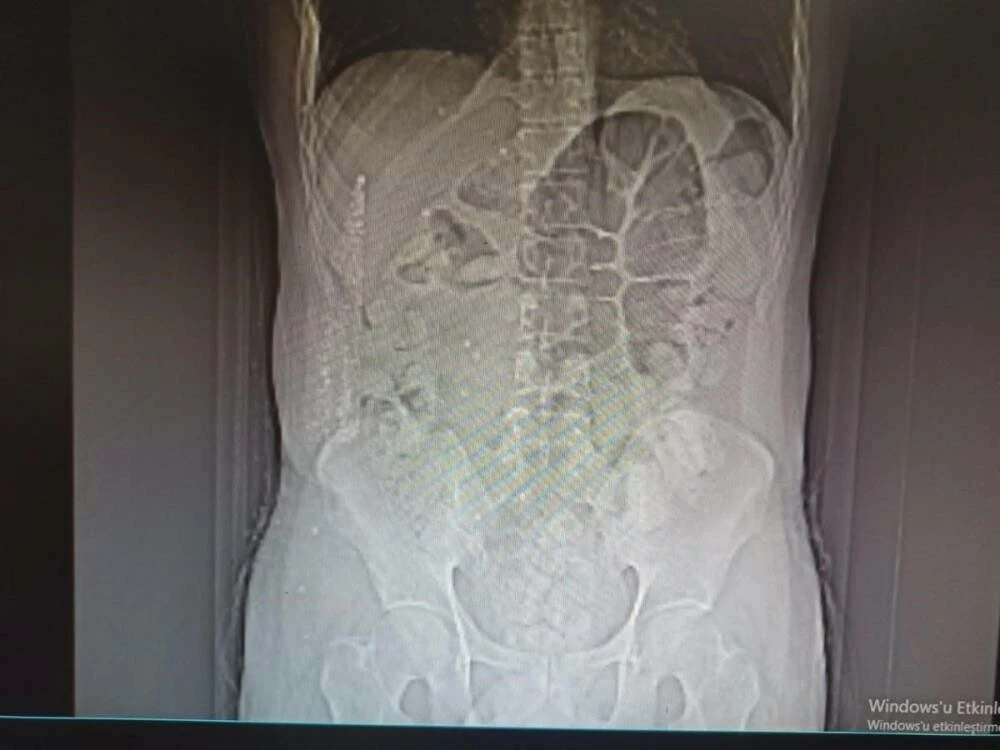

İhlas Haber Ajansı'nın haberine göre, İl Emniyet Müdürlüğü Narkotik Suçlarla Mücadele Şube Müdürlüğü ile Kaçakçılık ve Organize Suçlarla Mücadele Şube Müdürlüğü ekiplerince yapılan ortak çalışmasında uygulama noktasında durdurulan, İran otobüsünde yolcu olarak bulunan İran uyruklu şüpheli 31 yaşındaki M.K. isimli kişiye yapılan tomografi çekiminde mide ve bağırsak kısmında uyuşturucu olabileceğini değerlendirilen çok sayıda yabancı cismin olduğu tespit edildi.

Yapılan tetkikler neticesinde M.K.’nın midesinden 64 parça halinde 711,86 gr gelen Afyon Sakızı ele geçirildi. Şüpheli M.K. emniyetteki işlemlerinin ardından sevk edildiği adliyede tutuklanarak cezaevine gönderildi.